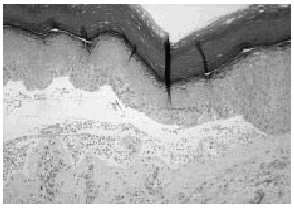

Se realizó una biopsia de una de las lesiones que demostró la existencia de una ampolla subepidérmica en cuya base se conservaba el festoneado de las papilas dérmicas, con un escaso infiltrado inflamatorio en dermis (Fig. 2). La inmunoflourescencia directa fue negativa. Los estudios de laboratorio fueron normales, incluyendo la determinación de porfirinas plasmáticas, uro y coproporfirinas, pruebas hepáticas y autoanticuerpos.

FIG. 2.--Ampolla subepidérmica que conserva el festoneado de las papilas dérmicas y presenta un escaso infiltrado inflamatorio en dermis papilar.